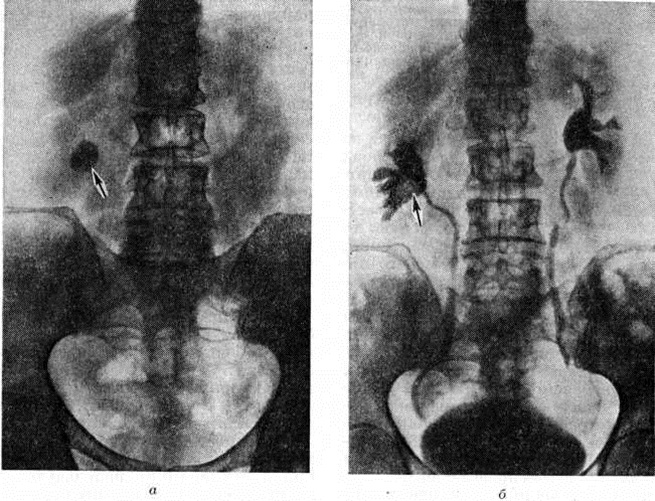

Рис. 2.

Обзорная рентгенограмма брюшной полости больного почечнокаменной болезнью в сочетании с желчнокаменной болезнью: 1 — множественные фасетчатые камни в желчном пузыре, 2 — коралловидный камень в правой почке.

Рентгенограммы брюшной полости и таза больного почечнокаменной болезнью: а обзорная рентгенограмма, в лоханке правой почки стрелкой указана округлая тень камня; о экскреторная урограмма, видны расширенные чашечки и лоханка правой почки; дефект наполнения, обусловленный камнем, указан стрелкой.

Информация об Ordo Deus Перейти в оглавление сайта

Рентгенологические метод является основным в диагностике Почечнокаменная болезнь Он позволяет выявить не только наличие камней, но и установить их форму, величину, локализацию, структуру, а также получить представление об изменениях в анатомо-функциональном состоянии почек и мочевых путей. Исследование начинают с обзорной рентгенографии брюшной полости, начиная от ThXl до лонного сочленения. Обнаружение на обзорной рентгенограмме тени, подозрительной на конкремент, не требует дифференциальной диагностики только в случае коралловидного камня, являющегося слепком чашечно-лоханочной системы (рисунок 2). Камни почечных чашечек представляют собой их слепки или имеют неправильную, округлую форму; камни почечной лоханки часто округлые или треугольные; камни мочеточника — цилиндрической, веретенообразной или неправильной формы. При аномалиях мочевых путей конкремент может находиться вне обычной локализации почек и других органов мочеполовой системы. Обнаружение камня на снимке зависит от его размеров, химический состава и локализации. Наиболее интенсивное изображение дают оксалаты, затем камни смешанного состава и фосфаты. Оксалаты имеют шиповидные, фестончатые контуры и напоминают тутовую ягоду. Коралловидные камни чаще всего компактны, но могут быть слоистыми, как и остальные конкременты смешанного состава, иногда они достигают гигантских размеров. Слоистое строение камней на рентгенограммах обусловлено различной проницаемостью для рентгеновского излучения составляющих их солей. Около 10% камней с низким атомным весом (ураты, белковые, цистиновые и ксантиновые камни) не видны или дают неотчётливую тень. Особенно трудно выявить камни, проецирующиеся на костный скелет (ребра, поперечные отростки позвонков, крестцово-подвздошные сочленения). Для их обнаружения производят прицельные снимки в косых и атипичных проекциях, томо или зонографию. Томография (смотри полный свод знаний), применяемая самостоятельно или в сочетании с контрастными исследованиями, показана при недостаточной подготовке больного к рентгенологическое исследованиям, почечной колике, сопровождающейся парезом кишечника, или при малых размерах камней. Поскольку при Почечнокаменная болезнь довольно часто конкременты самопроизвольно отходят из чашечно-лоханочной системы, они могут проецироваться по ходу мочеточника паравертебрально, имеют тенденцию задерживаться над одним из его анатомических сужений. Наиболее важные сведения о принадлежности выявленной тени к мочевым путям, о локализации камня, вызванных им нарушениях функции почек, уродинамики, анатомического состояния мочевых путей (гидрокаликоз, пиелэктазия, гидроуретеронефроз — расширение чашечек, лоханки, мочеточника и почки) выявляются при экскреторной урографии (рисунок 3, б) с предварительной обзорной рентгенографией (рисунок 3, а). Она позволяет установить вид лоханки (открытая или закрытая, внутрипочечная или внепочечная), состояние лоханочно-мочеточникового сегмента (смотри полный свод знаний: Пиелография). Обычно рентгенопозитивный конкремент определяется в мочевых путях, но иногда его изображение перекрывается, как бы тонет на фоне контрастированной мочи, особенно при небольшом камне или малой интенсивности его изображения. При рентгенонегативных камнях виден дефект наполнения мочевых путей (в том числе и лоханки) с чёткими контурами (рисунок 4). В отличие от опухоли лоханки в косых проекциях вокруг камня сохраняется ободок контрастного вещества. Обычно при камнях лоханки, достигающих в диаметре 3 сантиметров и более, наблюдаются пиелэктазия и гидрокаликоз. Произведённые в процессе экскреторной урографии телевизионная пиелоуретероскопия в сочетании с кинематографией или видеомагнитофонной записью изображения позволяют оценить нарушения тонуса и моторной функции верхних мочевых путей при камнях, отличить спастические, функциональный процессы от органических. Если спустившийся в мочеточник камень частично закрывает его, то отмечаются расширение мочеточника и лоханки (пиелоуретерэктазия) выше уровня расположения конкремента. На экскреторных урограммах, произведённых во время почечной колики, выявляется увеличенная почка с усиленным нефрографическим эффектом без контрастирования чашечно-лоханочной системы и мочеточника — так называемый большая белая почка. Такая рентгенологическое картина указывает, что функция почки сохранена. При длительной полной блокаде камнем (более 3—4 недель) функция почки из-за атрофии снижается и может полностью утрачиваться. На экскреторных урограммах, произведённых после почечной колики, иногда наблюдается проникновение контрастированной мочи за пределы мочевых путей, а также лоханочно-почечный рефлюкс. Ретроградную пиелоуретерографию с жидким контрастным веществом или кислородом производят только при значительном снижении функции почек, при сомнении в диагнозе, особенно в тех случаях, когда при экскреторной урографии не выявляется рентгенонегативный камень. Рентгенографию мочеточника после введения в него катетера производят в прямой и косой проекциях. Если при этом тень, подозрительная на камень, на обоих снимках находится рядом с катетером или сливается с его тенью, то диагноз Почечнокаменная болезнь не вызывает сомнений. Тень, не относящаяся к мочеточнику, определяется на некотором расстоянии от катетера. На ретроградных пиелограммах с жидким контрастным веществом небольшой концентрации рентгенонегативные камни выявляются в виде дефекта наполнения. Особенно демонстративными такие камни становятся при пневмопиелорентгенографии или пневмопиелотомографии (рисунок 5). С помощью ретроградной уретерографии удаётся выявить рентгенонегативный камень в мочеточнике, верхние границы дефекта при этом имеют вогнутую форму (рисунок 6).